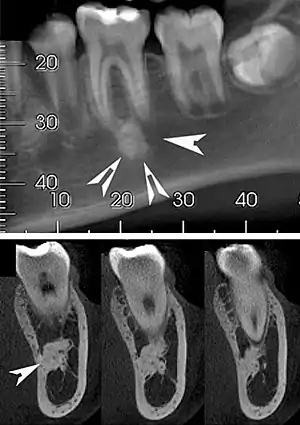

| Top: A hyperdense round lesion located under the apex of a non-infected tooth. Bottom: The lesion is separated from the root of the adjacent tooth by a visible periodontal membrane.[1] | |

Idiopathic osteosclerosis, also known as enostosis or dense bone island, is a condition which may be found around the roots of a tooth, usually a premolar or molar.[2] It is usually painless and found during routine radiographs as an amorphous radiopaque (light) area around a tooth. There is no sign of inflammation of the tooth, and if the island is associated with the root the periodontal ligament space is preserved.[2]

Well defined, rounded or triangular radiodensity, that is uniformly opaque. There is no lucent component. Found near the root apex or in the inter-radicular area. Root resorption and tooth movement are rare. If it blends into bone cortices, it does so with no expansion or thinning.[2]